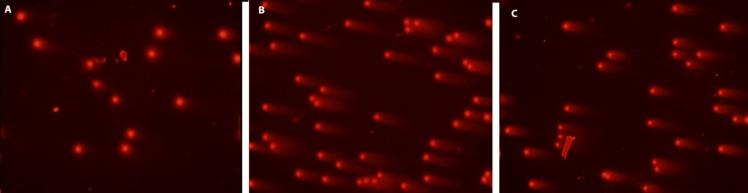

The present study investigates the antioxidant, anticancer, anticholinesterase, anti-genotoxic activities and phenolic contents of flower, fruit and seed methanol extracts of AUCHER. The amounts of protocatechuic acid, catechin, caffeic acid and syringic acid in methanol extracts were determined by HPLC. Total phenolic content of seed extract was found more than fruit and flower extracts. The DPPH free radical scavenging activity of flower and seed methanol extracts showed close activity versus BHT as control. Among three extracts of only flower methanol extract was exhibited considerable cytotoxic activities against to HeLa and NRK-52E cell lines. Moreover, seed methanol extract showed both acetyl and butyrl-cholinesterase inhibitory activity. The highest anti-genotoxic effects were seen 25 and 50 μg/mL concentrations. In this study, the extracts showed a strong antioxidant and anti-genotoxic effect. The seed extract was more efficient- than extracts of fruit and flowers. Our results suggest that the antioxidant and anti-genotoxic effects of extracts depend on their phenolic contents. Further studies should evaluate the and the benefits of seed methanol extracts.

本研究调查了奥氏蔷薇花、果实和种子甲醇提取物的抗氧化、抗癌、抗胆碱酯酶、抗基因毒性活性及酚类成分。通过高效液相色谱法测定甲醇提取物中原儿茶酸、儿茶素、咖啡酸和丁香酸的含量。发现种子提取物的总酚含量高于果实和花提取物。花和种子甲醇提取物的DPPH自由基清除活性与作为对照的丁基羟基甲苯表现出相近的活性。在三种提取物中,只有花甲醇提取物对HeLa和NRK-52E细胞系表现出显著的细胞毒性活性。此外,种子甲醇提取物表现出乙酰胆碱酯酶和丁酰胆碱酯酶抑制活性。在25和50μg/mL浓度下观察到最高的抗基因毒性作用。在本研究中,提取物表现出强大的抗氧化和抗基因毒性作用。种子提取物比果实和花提取物更有效。我们的结果表明,提取物的抗氧化和抗基因毒性作用取决于其酚类成分。进一步的研究应评估种子甲醇提取物的……及其益处。